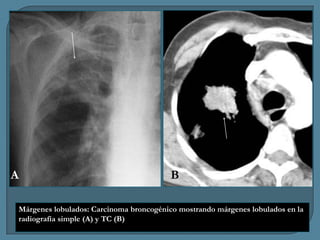

A

B

Márgenes lobulados: Carcinoma broncogénico mostrando márgenes lobulados en la

radiografía simple (A) y TC (B)